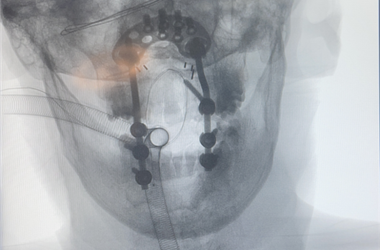

掌骨(gu)(gu)(gu)骨(gu)(gu)(gu)折是(shi)手部常見(jian)骨(gu)(gu)(gu)折之(zhi)一,多為直接暴力引起。由(you)于(yu)骨(gu)(gu)(gu)間肌(ji)、蚓狀肌(ji)和屈(qu)指肌(ji)的(de)牽拉(la),骨(gu)(gu)(gu)折端向背(bei)側成角。依據外傷史,手背(bei)腫脹、疼痛(tong)、畸(ji)形(xing)、局(ju)部壓(ya)痛(tong)等(deng)表(biao)現,結合X線片檢查(cha)診(zhen)斷可確診(zhen)。